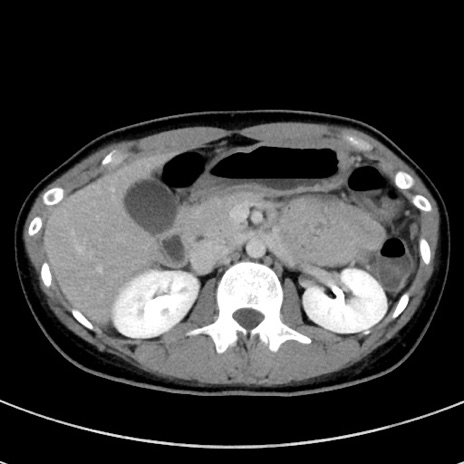

冠状断像

【症例】20歳代女性

【主訴】嘔吐、下腹部痛

【現病歴】昨日夕食後に嘔吐し下腹部痛が出現。本日になっても嘔吐持続し改善しないため来院。

【身体所見】意識清明、BT 37.2℃、BP 108/67mmHg、腹部:平坦、やや硬、下腹部正中から右にかけて圧痛あり、反跳痛軽度あり、tapping pain(+)。

【データ】WBC 13600、CRP 14.94